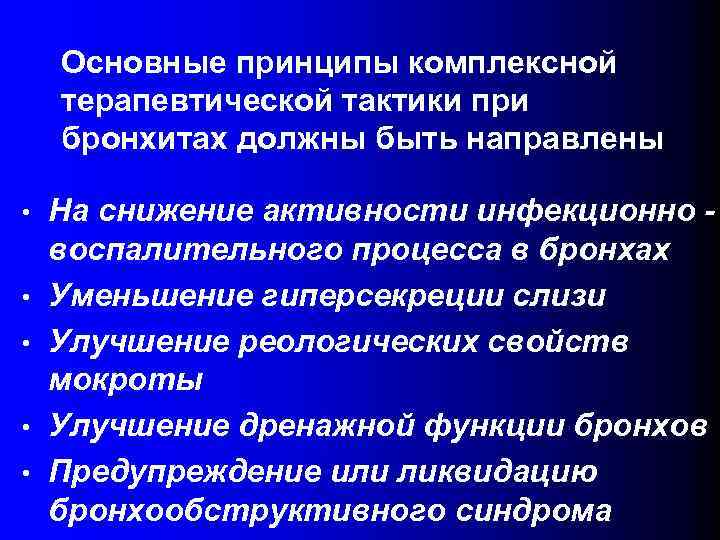

Основные принципы комплексной терапевтической тактики при бронхитах должны быть направлены • • • На снижение активности инфекционно воспалительного процесса в бронхах Уменьшение гиперсекреции слизи Улучшение реологических свойств мокроты Улучшение дренажной функции бронхов Предупреждение или ликвидацию бронхообструктивного синдрома